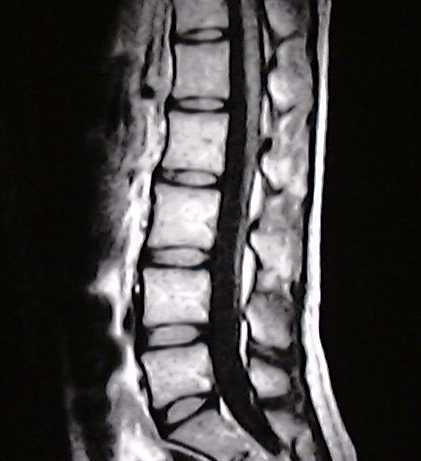

椎間板ヘルニア

脊柱管狭窄症

坐骨神経痛

このような病名をつけられて

このような病名をネットや本やテレビで調べていますよね?

何を言いたいかというと、画像上の問題(ヘルニアなど)はあくまで結果で

原因ではないです。

痛みがない人でもヘルニアあるんですよ。

1.椎間板ヘルニアや脊柱管狭窄症がシビレや痛みの原因ではないのです

画像診断を見てこれが飛び出て神経に……なんて言われたらこれが原因と思うのも無理はないでしょう

でもですね、これが原因と診断された患者様がなぜ当院の施術で良くなるのでしょうか